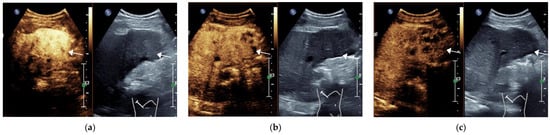

3.1. General Information of the Patient and CEUS Features of the Lesions

3.2. Final Results of CEUS LI-RADS Category of Lesions